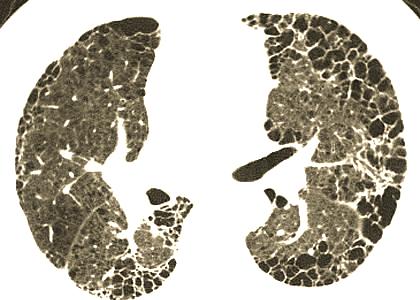

CT 检查结果显示,翟女士肺部出现 “双肺间质性纤维化待排”。要知道,半年前翟女士体检时做过胸部 CT,当时肺部并未发现任何病变。但由于这次检查结果异常,在肩部手术顺利结束后,翟女士转入医院其他科室,对 “双肺间质性纤维化” 进行诊断治疗。经过数日住院检查,最终被诊断为 “特发性肺间质纤维化”。

可能很多朋友不太了解 “特发性肺间质纤维化” 这个病根据相关资料,它是一种以呼吸困难和肺功能进行性恶化为特征的病因不明的慢性纤维化性间质性肺疾病,中位生存时间约 2 至 4 年,被不少人称为 “慢性绝症”。得知母亲患了这样的病,翟先生一家瞬间陷入了巨大的悲痛之中。

此后翟先生还带母亲到其他医院就诊,医生表示根据之前体检的 CT 和后来的 CT 对比,病情不应该发展如此之快,但后来的 CT 又确实显示双肺间质性纤维化,半年前没有这个病,但是半年后检查结果CT得病了,医院的医生义无反顾的选择了相信CT报告,就是没有怀疑CT出问题了。

就这样,翟女士开始按医嘱服用抗纤维化的药物尼达尼布。一直到 6 月 17 日,翟女士再次到医院复查,审核报告的医生在调阅 2 月 28 日的胸部 CT 进行对比时,发现两次 CT 图像不匹配,这才确认 2 月 28 日的胸部 CT 图像并非翟女士本人的。也就是说,翟女士被误诊了,而且已经服用了约 3 个月的药物。